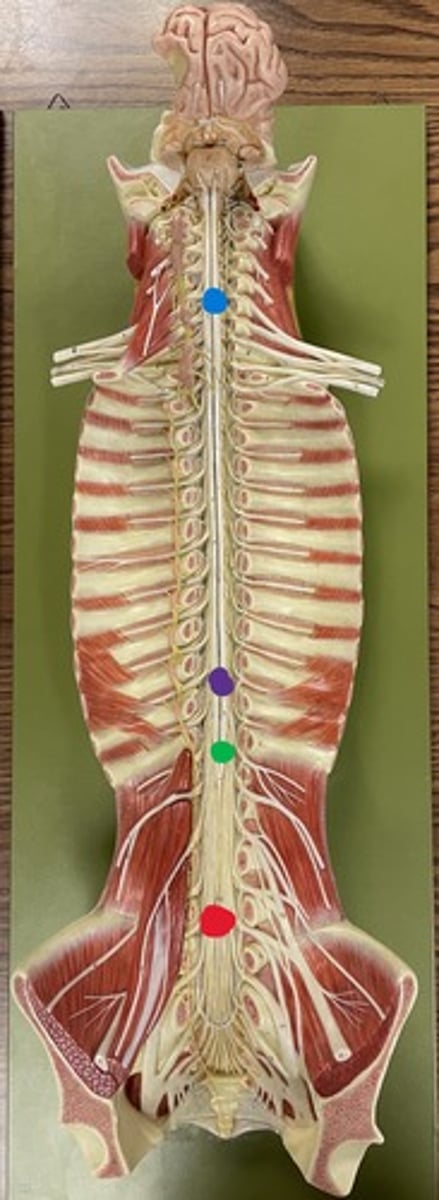

Cervical enlargement

Blue

Lumbar enlargement

Purple

Conus medullaris

Green

Cauda equina

Red

Filum terminale

blue